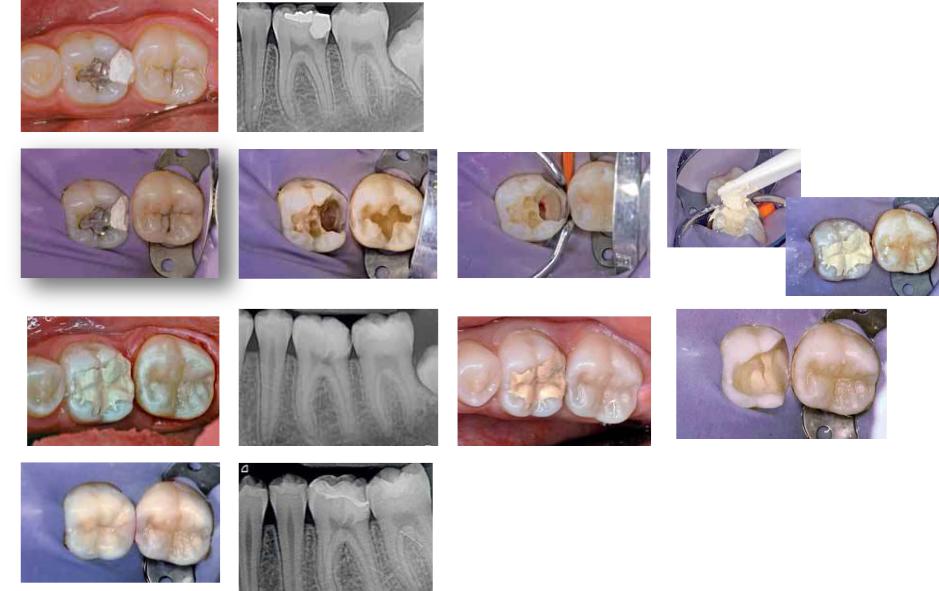

Прямое покрытие пульпы

После некрэктомии глубокой кариозной полости при язвенном пульпите вскрыт рог пульпы.

На вскрытый рог пульпы нижнего моляра накладывается МТА и стеклоиономерный цемент.

Через год почти сформировались корни, перфорационное отверстие закрылось заместительным дентином. [Dentsply].

Показания При реставрации зубов

Временная пломба

Лечебная/изолирующая подкладка под реставрацию при глубоком или обширном кариесе (при сэндвич технике).

Реставрация при лечении пришеечных или корневых кариозных разрушениях.

Прямое покрытие пульпы.

Непрямое покрытие пульпы.

Отпрепарирован под вкладку

Через 2 мес после применения

Биодентина

Biodentine™

Показания

При эндодонтическом лечении

Устранение перфораций корня.

Устранение фуркационных перфораций.

Устранение внутренних резорбций.

Устранение наружных резорбций.

Апексификация.

Закрытие верхушки корня после ее резекции (ретроградное пломбирование).